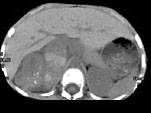

- 多项选择题男,5 岁, 消瘦、贫血、纳差和腹部包块3个月,CT检查如图, 下列说法正确的是  (    )

- A、右侧腹腔内可见一巨大软组织肿块影,其边界欠清楚

- B、肿块密度不均匀,可见片状的较高密度,考虑为出血,也可见点状的钙化影

- C、该病灶来源于肝脏,考虑为肝母细胞瘤

- D、该病灶来源于右肾上腺,考虑为神经母细胞瘤

- E、该病灶来源于右肾,考虑为肾胚胎瘤